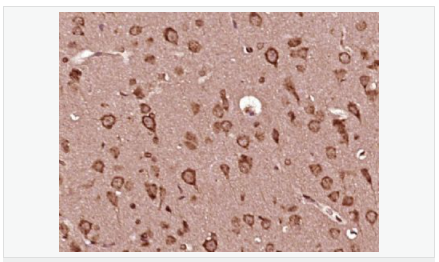

產(chǎn)品應(yīng)用WB=1:500-2000 ELISA=1:5000-10000 IHC-P=1:100-500 (石蠟切片需做抗原修復(fù))

產(chǎn)品介紹This gene encodes a polypeptide hormone precursor that undergoes extensive, tissue-specific, post-translational processing via cleavage by subtilisin-like enzymes known as prohormone convertases. There are eight potential cleavage sites within the polypeptide precursor and, depending on tissue type and the available convertases, processing may yield as many as ten biologically active peptides involved in diverse cellular functions. The encoded protein is synthesized mainly in corticotroph cells of the anterior pituitary where four cleavage sites are used; adrenocorticotrophin, essential for normal steroidogenesis and the maintenance of normal adrenal weight, and lipotropin beta are the major end products. In other tissues, including the hypothalamus, placenta, and epithelium, all cleavage sites may be used, giving rise to peptides with roles in pain and energy homeostasis, melanocyte stimulation, and immune modulation. These include several distinct melanotropins, lipotropins, and endorphins that are contained within the adrenocorticotrophin and beta-lipotropin peptides. Mutations in this gene have been associated with early onset obesity, adrenal insufficiency, and red hair pigmentation. Alternatively spliced transcript variants encoding the same protein have been described. [provided by RefSeq, Jul 2008].